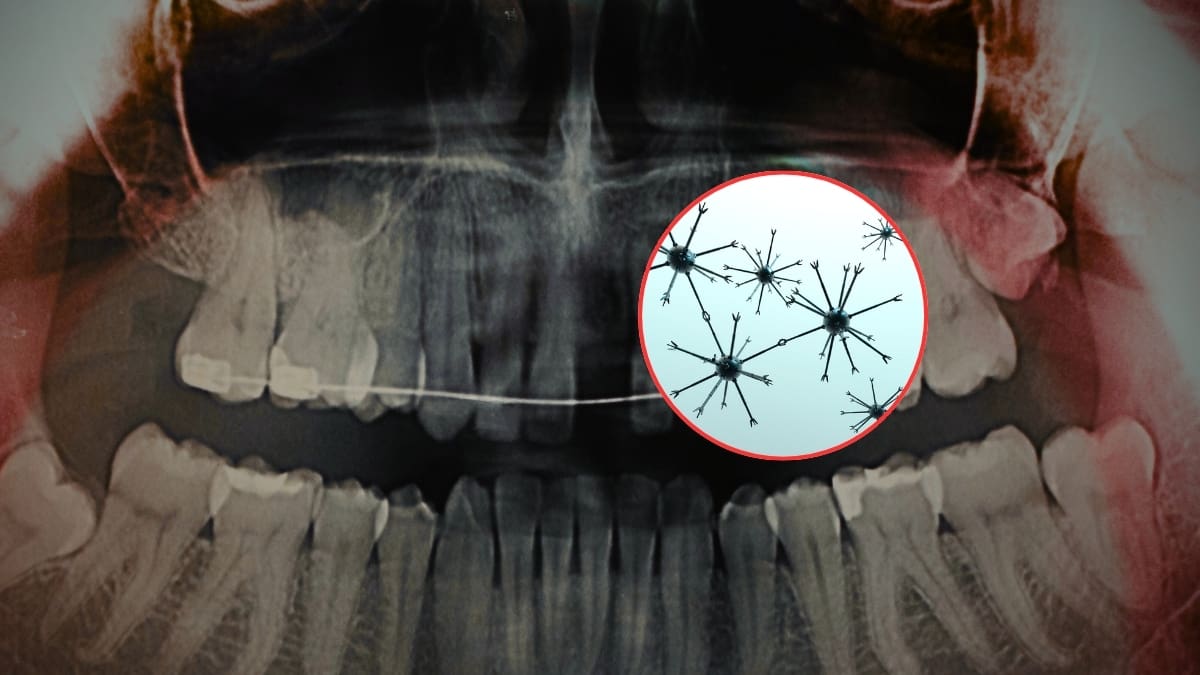

Científicos crearon nanorobots magnéticos para eliminar la sensibilidad dental en solo 20 minutos, penetrando hasta 500 micrómetros dentro del diente para sellar la dentina desde el interior, lo que daría alivio duradero sin necesidad de usar pastas especiales o ir al dentista

¿Adiós a la pasta desensibilizante? Estudio en Advanced Science revela que nanorobots magnéticos penetran hasta 500 micrómetros y bloquean el dolor dental desde el interior